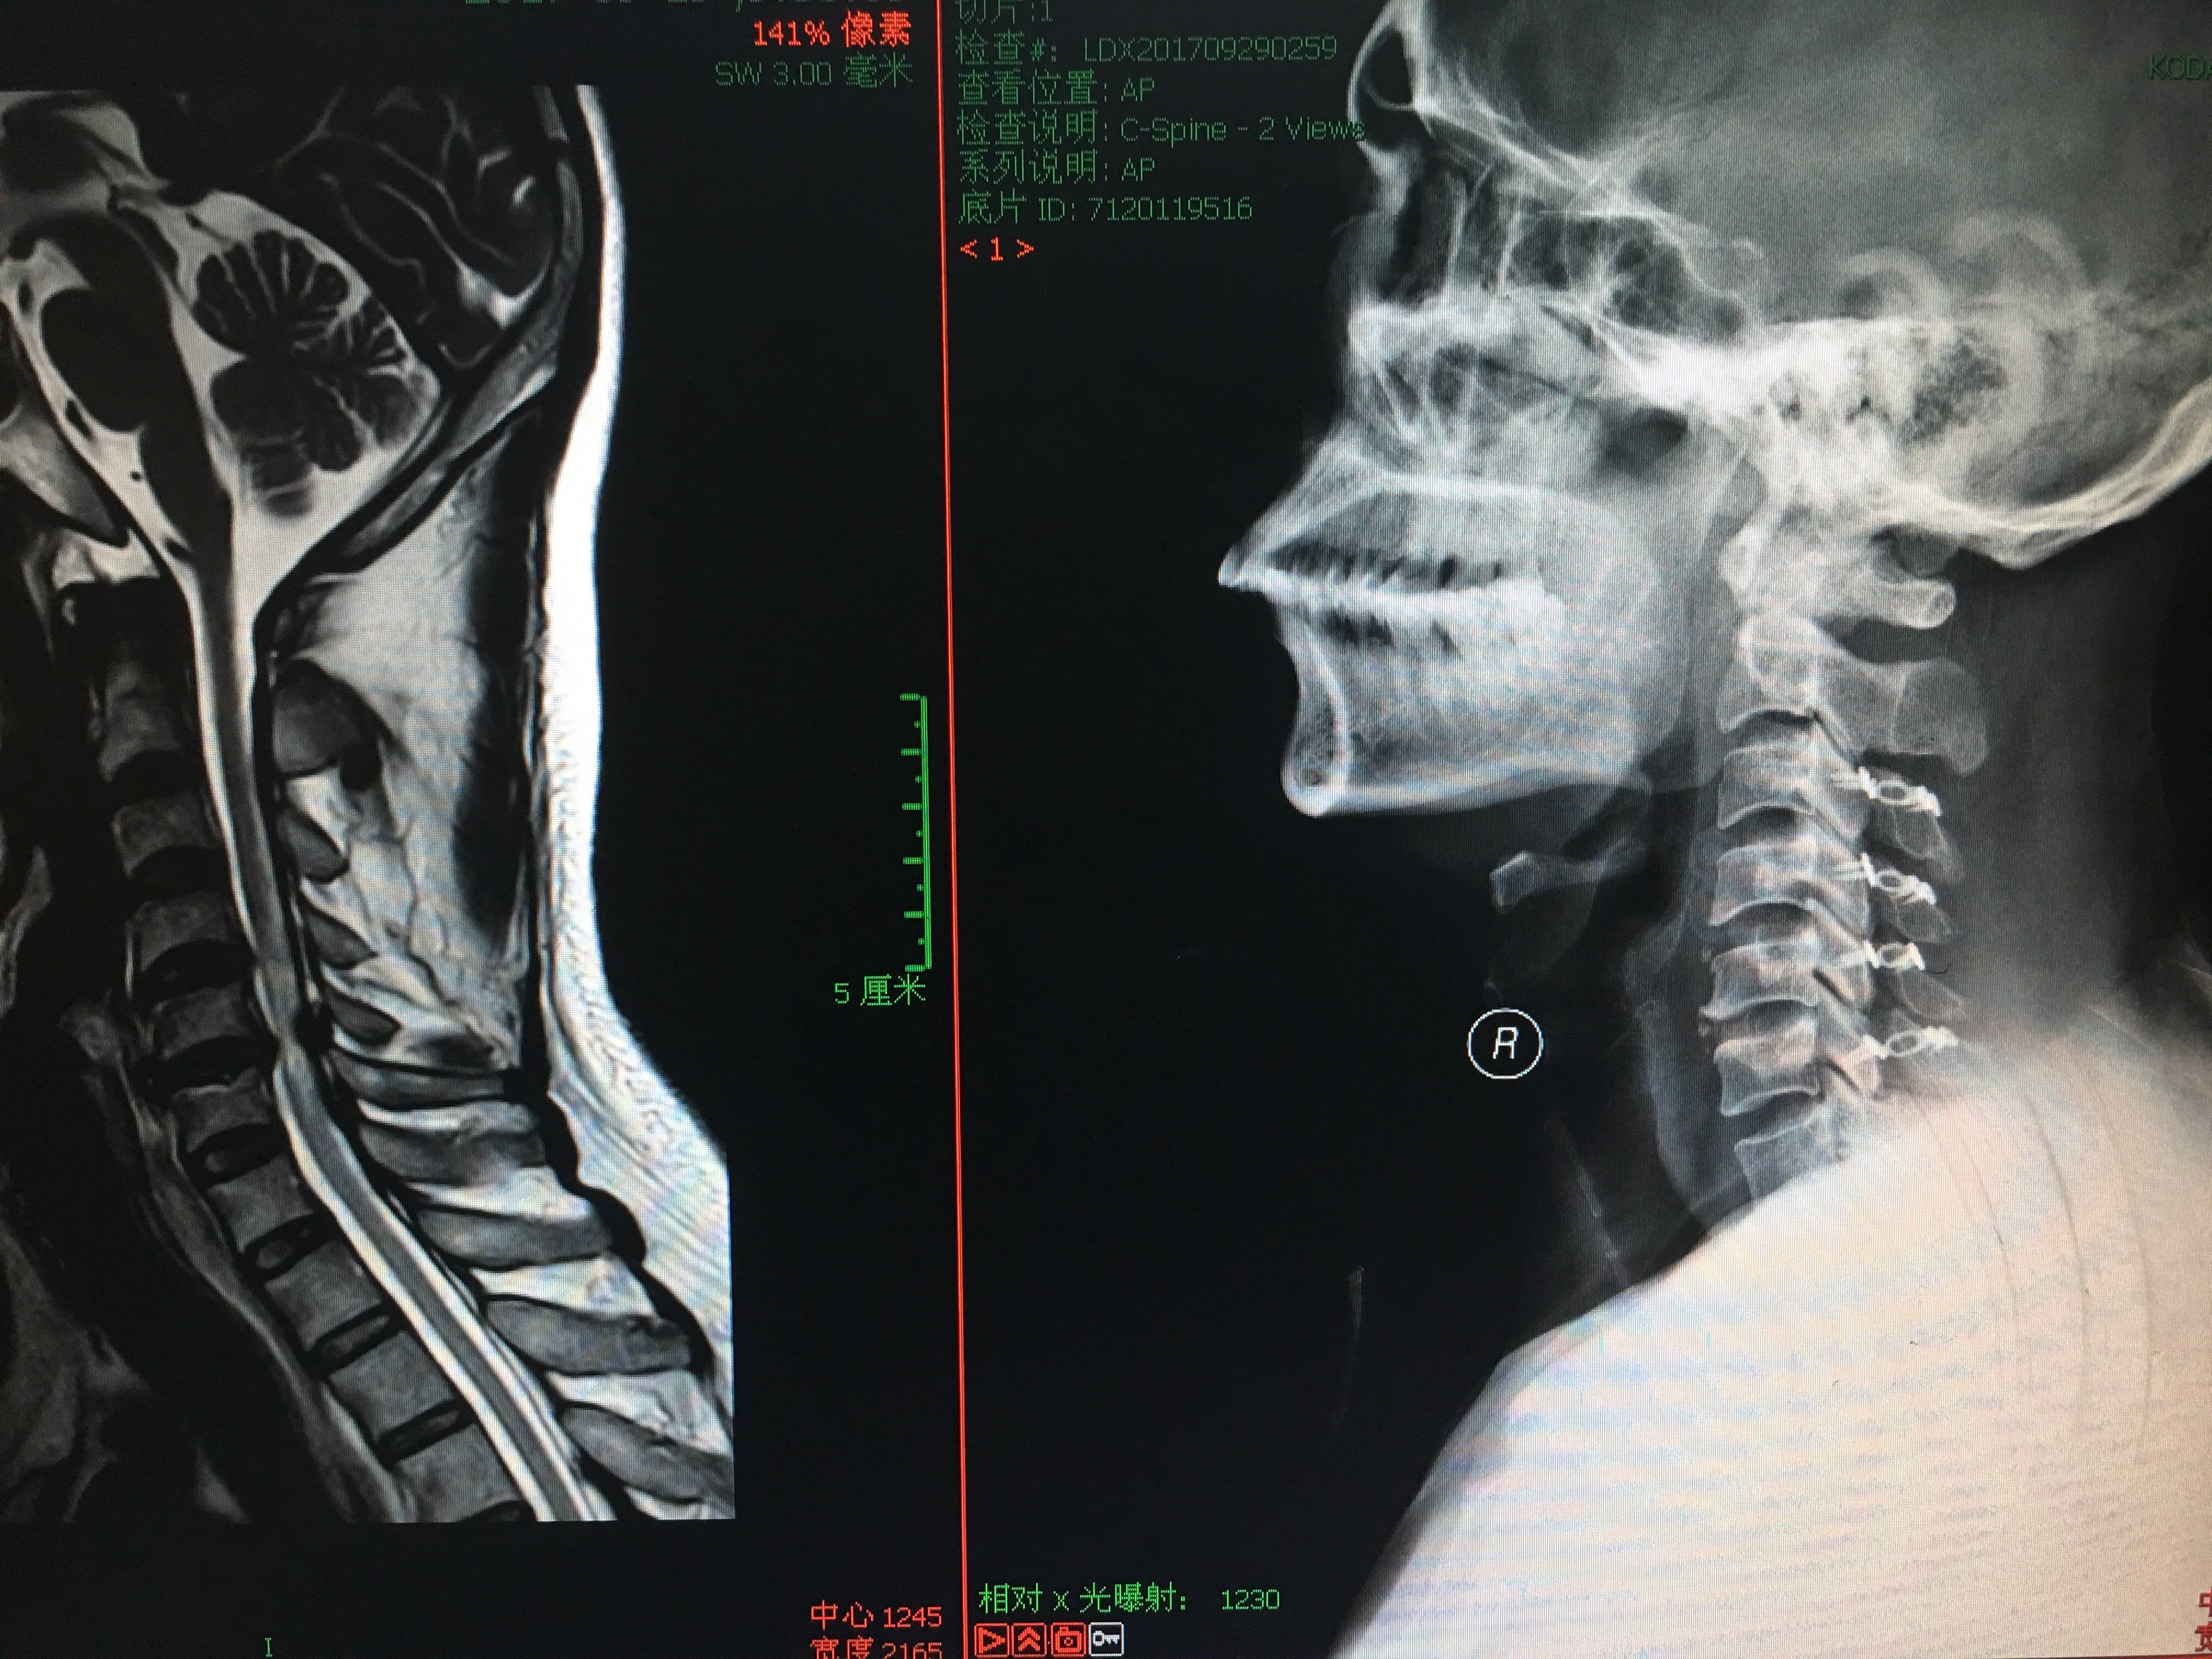

(3)X线检查:可出现颈椎生理前凸丧失或后突、椎间隙变窄、椎体边缘或钩突形成骨赘、项韧带钙化等症状。

4.脊髓空洞症:主要表现为感觉障碍,稍后出现运动障碍。 MRI可以清楚地显示脊髓中央管的增厚。